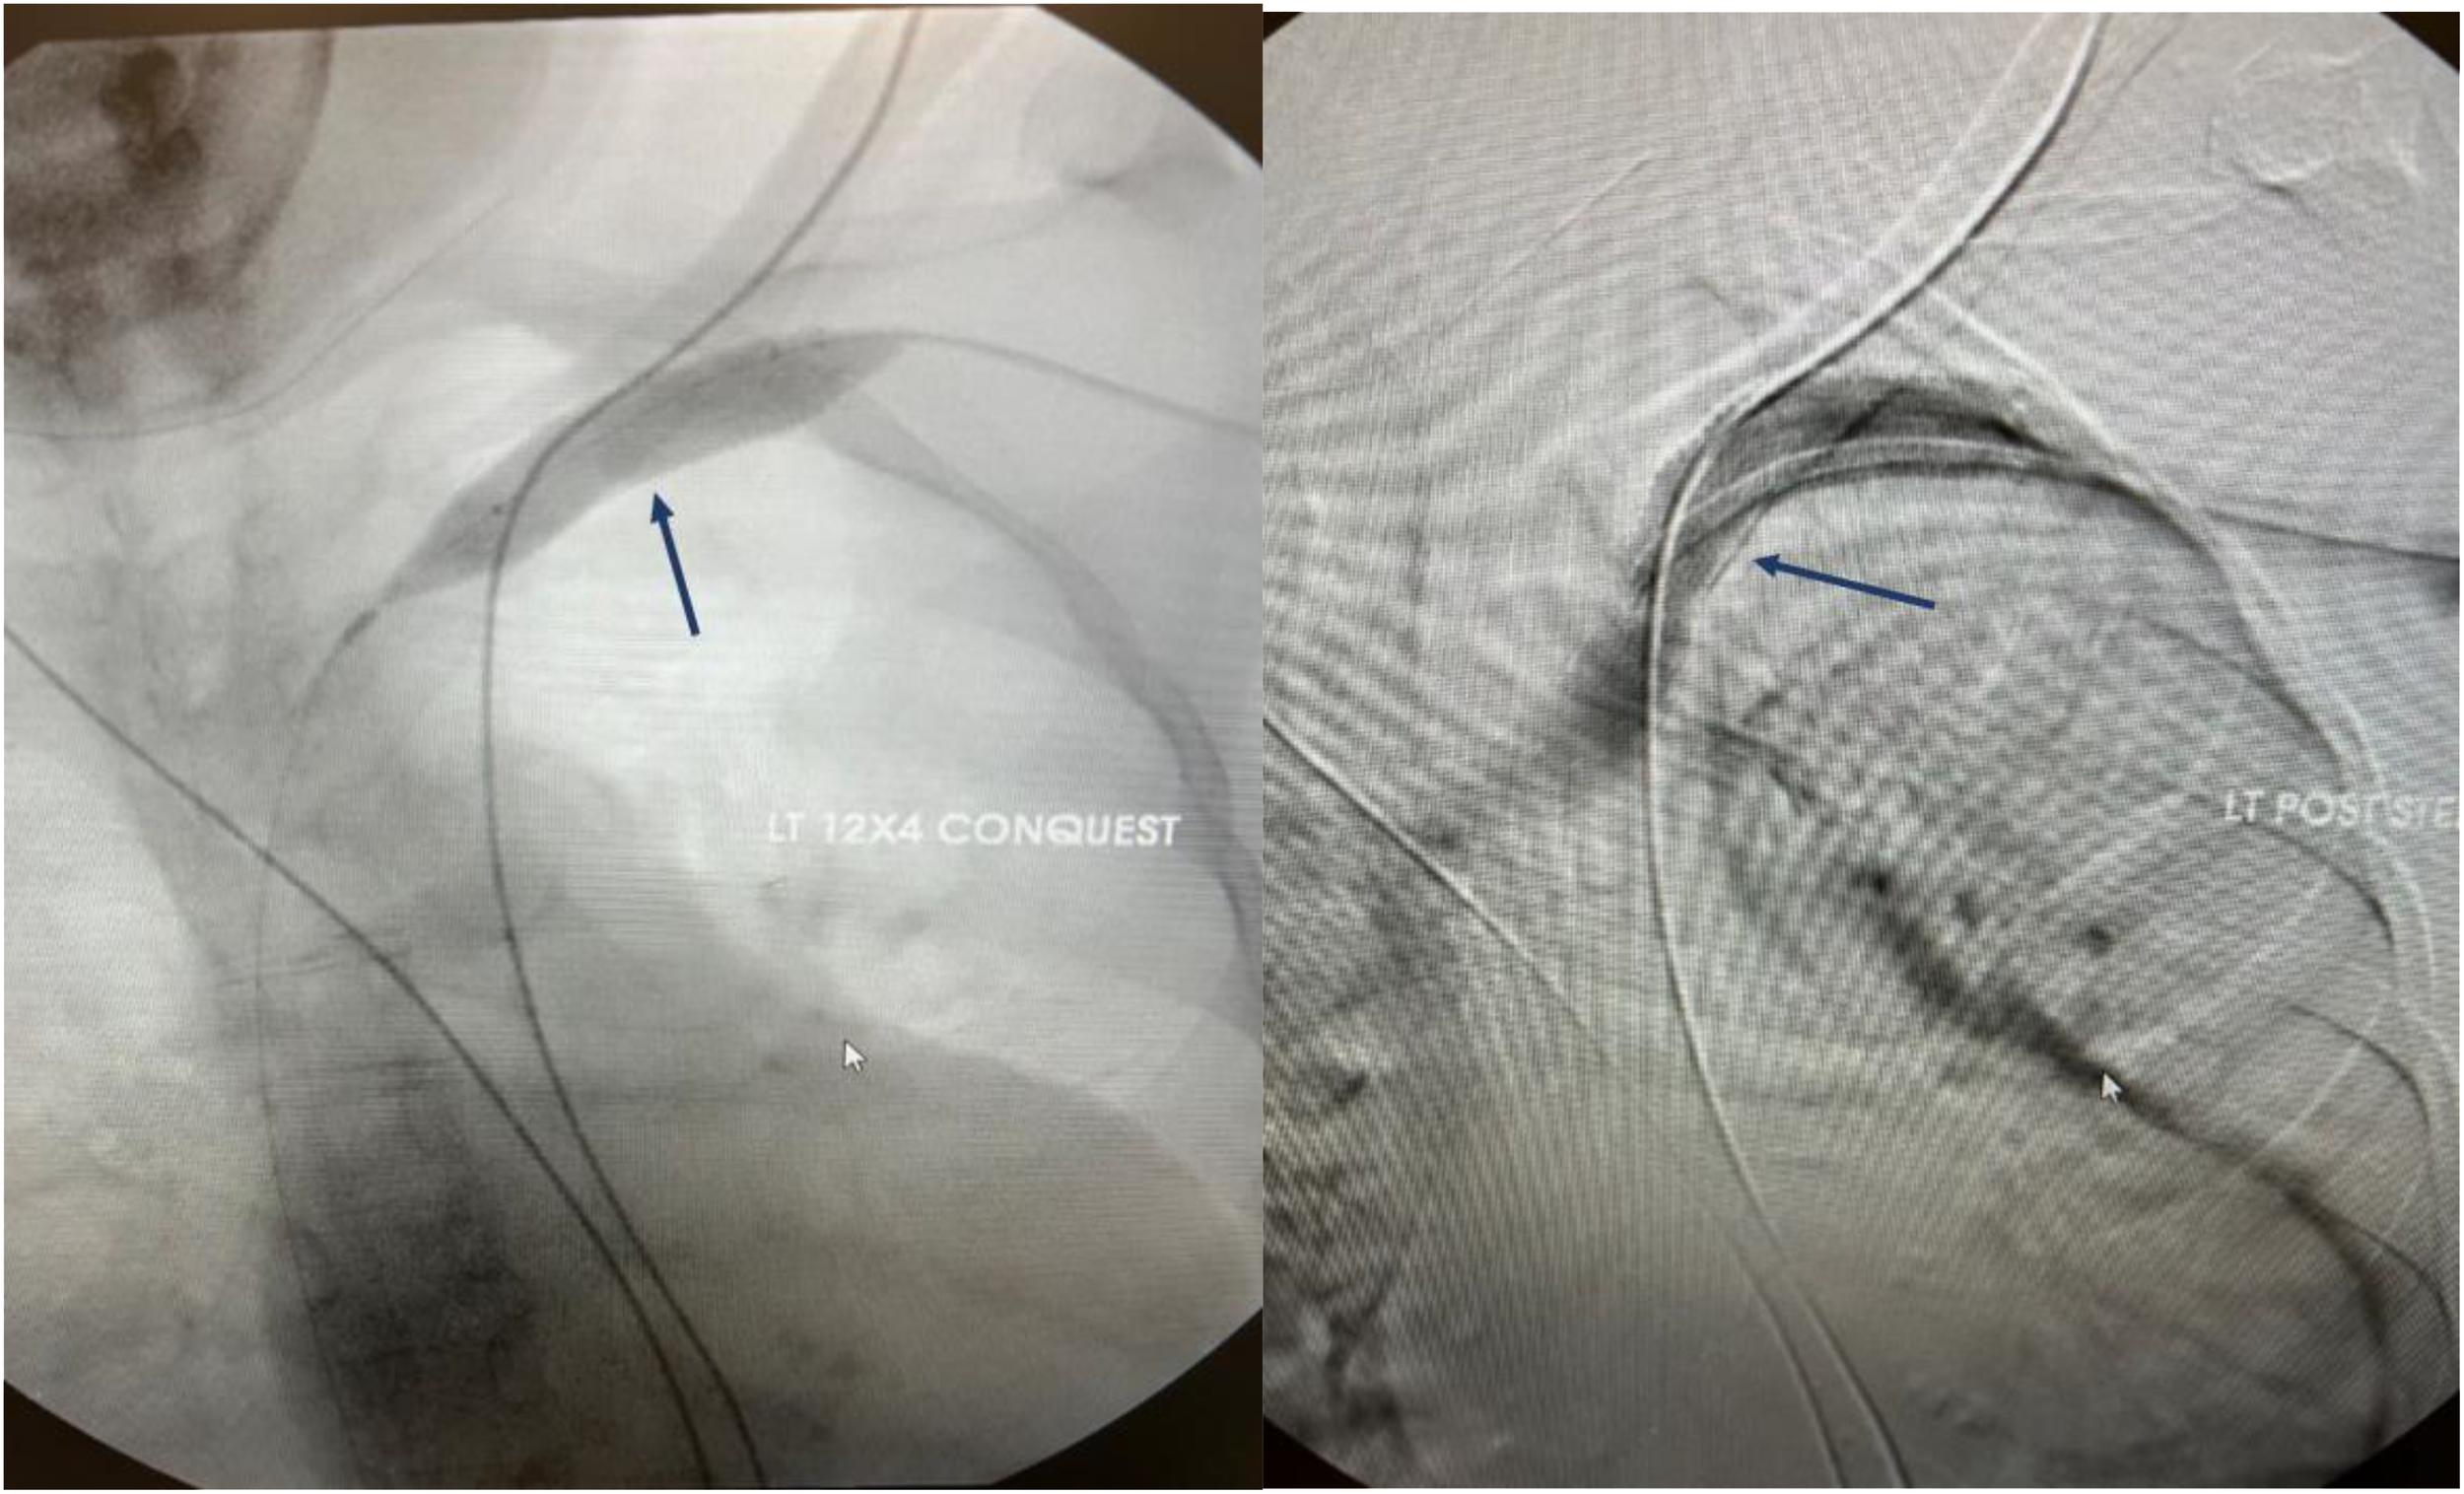

Angioplasty is the preferred treatment for symptomatic central vein stenosis (53) (Figure 5). The initial success rates, technical success, and complication rates are acceptable for PTA. No large, randomized trials have investigated PTA for the management of CVS. Based on the data from several studies, the reported technical success rate ranged from 70 to 90% (53–59). Unassisted patency rates following PTA ranged from 23% - 63% at 6 months, with cumulative patency rates ranging from 29%-100%. At 12 months, the unassisted patency rates were between 12% - 50% and 13-100% for cumulative patency (10, 54–59). However, these investigations employed different criteria to describe lesions, severity, and outcomes and were conducted in different demographics using diverse techniques resulting in substantial outcome heterogeneity (10, 54–59). Maintaining long-term patency and preventing occlusion necessitates repeated interventions due to a high recurrence rate. The high recurrence rate has partly been attributed to endothelial and vascular wall elasticity. Restenosis is not uncommon after endovascular interventions due to neointimal hyperplasia and often occurs at the same site (60). Angioplasty techniques require cracking and fissuring of the vessel intima, which can induce the recurrence of venous stenosis (61).

Figure 5

Angiographic representation of subclavian vein stenosis. The lesion was crossed with a sharp needle recanalization, then sequential a 10 x 8cm Conquest balloon was deployed followed by the 12x 4 cm Atlas balloon. A 13.5 x 10 cm Viabahn was ultimately deployed to maintain patency.